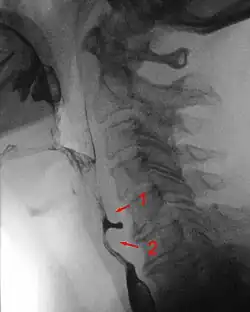

Radiologen teilen die Zenker-Divertikel nach Brombart in vier Stadien zunehmender Schwere ein:

- Stadium 1 ist eine dornenförmige, 2–3 mm lange Nischenbildung, die auch nicht immer sichtbar wird.

- Divertikel im Stadium 2 sind 7–8 mm groß und keulenförmig.

- Divertikel im Stadium 3 sind über 10 mm groß, sackförmig und nach unten umgebogen.

- Im Stadium 4 komprimiert das Divertikel die Speiseröhre und behindert sichtbar dessen Kontrastmittelpassage.[3]